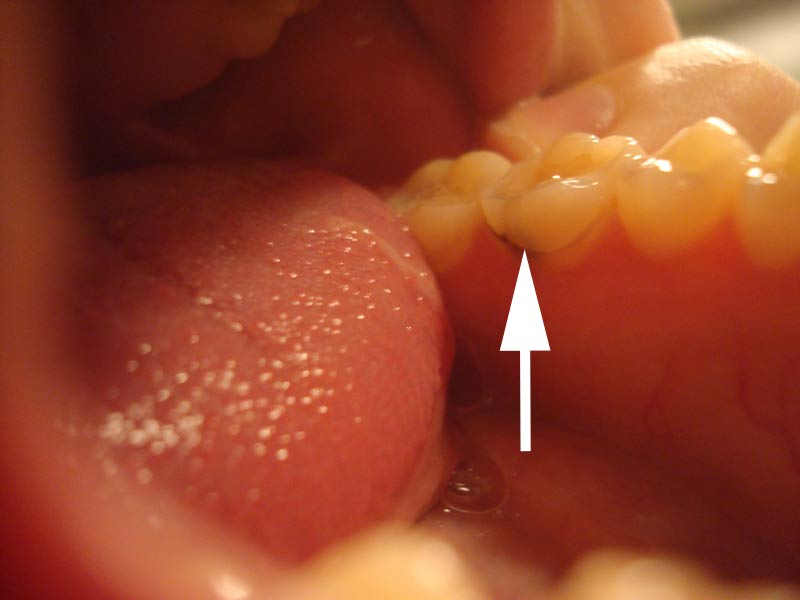

Oder eine Verfärbung?

Die Entfernung – sollte es Karies sein – ist kein Problem, zerbrechen Sie sich darüber nicht den Kopf … der Zahn hat dort wie scheint eine Fissur, entweder schimmert der Zahnstein so durch, oder es ist eben Karies …

Der Zahnarzt wird einfach von oben die Füllung aufbohren, somit opfert er keine Zahnhartsubstanz, so kann er leicht schauen ob es Karies ist oder nicht … vielleicht ist überhaupt kein bohren notwendig und man kann es klinisch feststellen …

Sollte es Karies sein, dann lassen Sie sich eine dauerhafte Versorgung machen – Sie sind jung – also ein Keramik-, Gold, oder Titaninlay z.B.